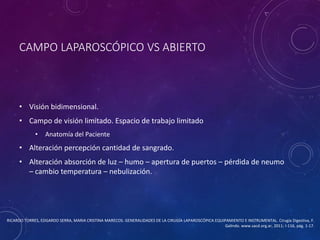

ANM CONACYT - Estado Del Arte de La Medicina Cirugia PDF, PDF, Cirugía

ANM CONACYT - Estado Del Arte de La Medicina Cirugia PDF, PDF, Cirugía